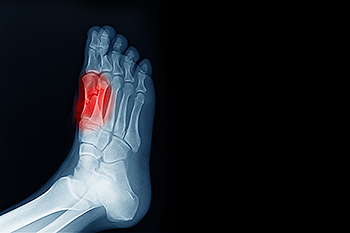

Common Foot Surgeries

Common Foot SurgeriesFoot pain can often be attributed to a number of conditions, including bunions, hammertoe, metatarsalgia, and neuromas, that require surgical intervention. Bunions are painful bony bumps on the side of the foot, caused by misalignment of the toe...